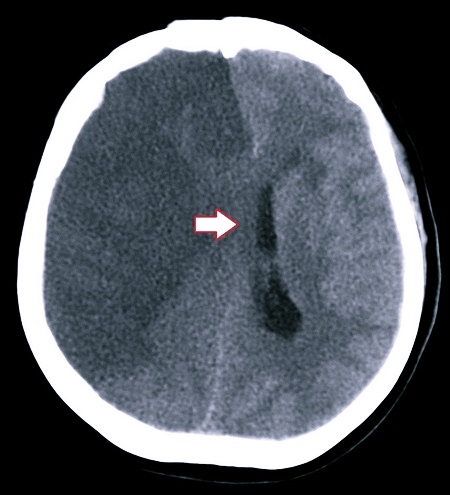

- Геморрагический инсульт, проникновение крови в субарахноидальное пространство.

Для диагностики заболевания используются различные современные методы: МРТ, КТ, УЗИ и многие другие. Если форма патологии не молниеносная, то заподозрить наличие заболевания может невролог, который отметит прогресс ухудшения состояния больного, наращивание процессов нарушения сознания вместе с симптоматикой менингита.

Чтобы подтвердить диагноз, используются методы магнитно-резонансной и компьютерной томографии.

Люмбальная пункция выполняется далеко не во всех случаях, потому что есть определенная опасность, что церебральные структуры в результате развивающегося отека сменили свое местоположение одновременно со сдавливанием ствола. Также помогают в постановке диагноза: биохимия крови, сбор анамнеза, анализ неврологического статуса, нейровизуализирующие обследования.